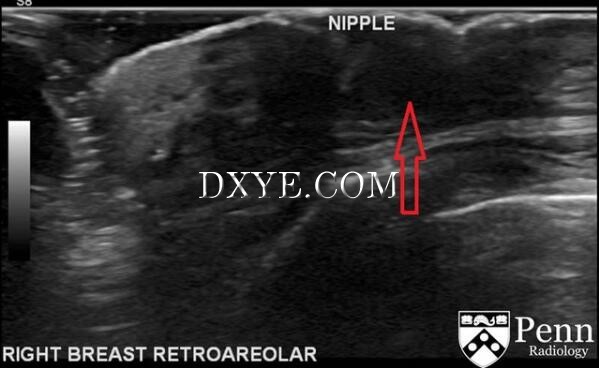

| 临床上多表现为累及乳头的皮肤改变,典型为湿疹样改变。现结合宾夕法尼亚大学的 Duke Duncan 医生在 auntminnie 上的病例来对该病进行介绍。 病史 54 岁女性,复发性单侧乳头淡黄色溢乳。 影像学检查 图 1 为钼靶侧斜位,乳腺皮肤增厚,乳头回缩,伴乳晕后方肿块引起组织变形(红色箭头),还可见多发性多形性钙化灶(黄色箭头) 图 2 为乳腺钼靶,乳腺皮肤增厚,乳头回缩,伴乳晕后方肿块引起组织变形(粉红色箭头)。还可见多发性多形性钙化灶(黄色箭头) 图 3 为乳腺钼靶,乳腺皮肤增厚,乳头回缩,伴乳晕后方肿块引起组织变形(红色箭头),还可见多发性多形性钙化灶(黄色箭头) 图 4 为乳腺超声,乳晕后方见一不规则肿块样低回声区(红色箭头),边缘模糊,后方见散射状声影 影像学发现 钼靶:呈不均匀致密型乳腺。乳腺皮肤增厚,乳头回缩,伴乳晕后方肿块引起组织变形。还可见多发性多形性钙化灶。 超声:乳晕后方见一不规则肿块样低回声区,边缘模糊,后方见散射状声影。 诊断 乳腺 Paget 病 鉴别诊断 乳头湿疹、乳腺佩吉特病(Paget)、炎性乳腺癌、乳晕下感染或脓肿 病例要点 乳腺 Paget 病是一种可侵犯乳头表面 / 表皮,导致乳头炎性样改变的恶性肿瘤。可为导管原位癌(DCIS)或浸润性导管癌(IDC)。首次由 James Paget 在 1874 年发现并以此命名。又称为乳头 Paget 病。 临床上多表现为累及乳头的皮肤改变,包括红斑、溃疡和湿疹样改变。可有血性或浆液性乳头溢液。 Paget 病是乳腺癌罕见的表现,约占所有乳腺癌的 1%~2%。大多数为女性,男性也可发病,50~60 岁多见。 影像学表现 钼靶:25%~50% 的病例钼靶无特异性表现。可表现为乳头后方肿块,伴组织结构紊乱和可疑钙化。还可有皮肤增厚和乳头改变。 超声:表现为乳头后方导管异常改变,伴钙化影和可疑肿块影。 MRI:乳头形态不规则,伴皮肤改变和乳头后方可疑强化灶。可确定病灶和受累的腋窝淋巴结。 治疗 取决于疾病范围。局部病灶采用保守治疗,恶性度较高的肿瘤采用乳房切除术和腋窝淋巴结清扫术。 |